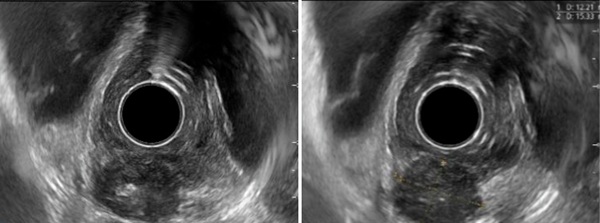

随后,我继续进行了超声内镜检查。

在病变部位扫查时,可以看到:

· 食管壁外有一个类圆形低回声病灶

· 低回声中央可见高回声区

· 病灶已经累及并侵透食管壁

这样的表现提示,病变很可能来源于食管旁淋巴结,并进一步侵犯食管壁。

结合胃镜表现,我更加确信自己的判断:

食管壁外低回声病灶,考虑淋巴结侵及食管壁,食管结核可能性大。

超声内镜表现